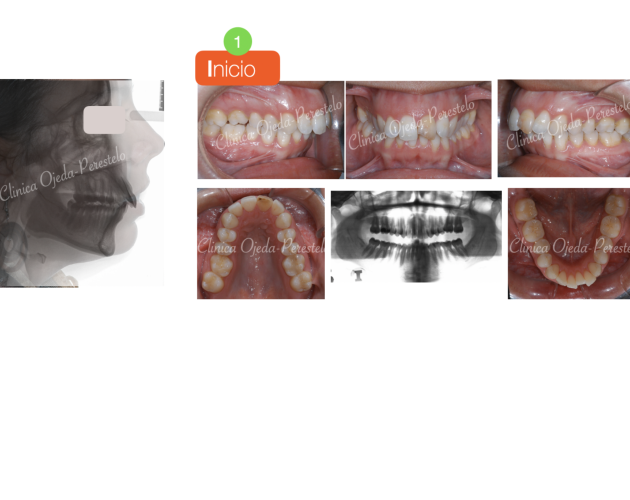

Casos de Éxito